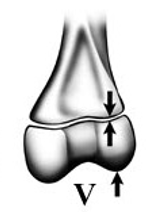

Grade the Salter-Harris fracture?

5 - compression upon physis

ERasure of the growth plate or compression